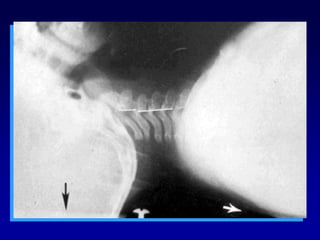

 Diagnóstico CLINICO

 Importante causa de muerte recuperable

en Trauma

 Requiere descompresión inmediata

 No Buscar hacer diagnóstico radiológico

TRAUMA PEDIATRICO

NEUMOTORAX A TENSION